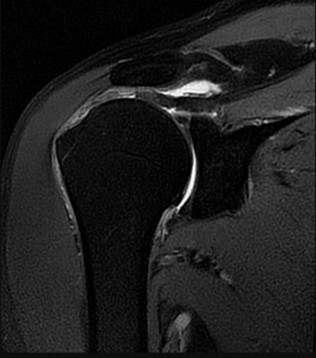

ORTHOPEDIC MCQS ONLINE OB 20 TRAUMA 2A OrthoCash 2020 A 25 year-old-male presents with the injury seen in Fi…

ORTHOPEDIC MCQS ONLINE OB 20 TRAUMA 2B CT angiography and admit the patient for hourly neurovascular checks …